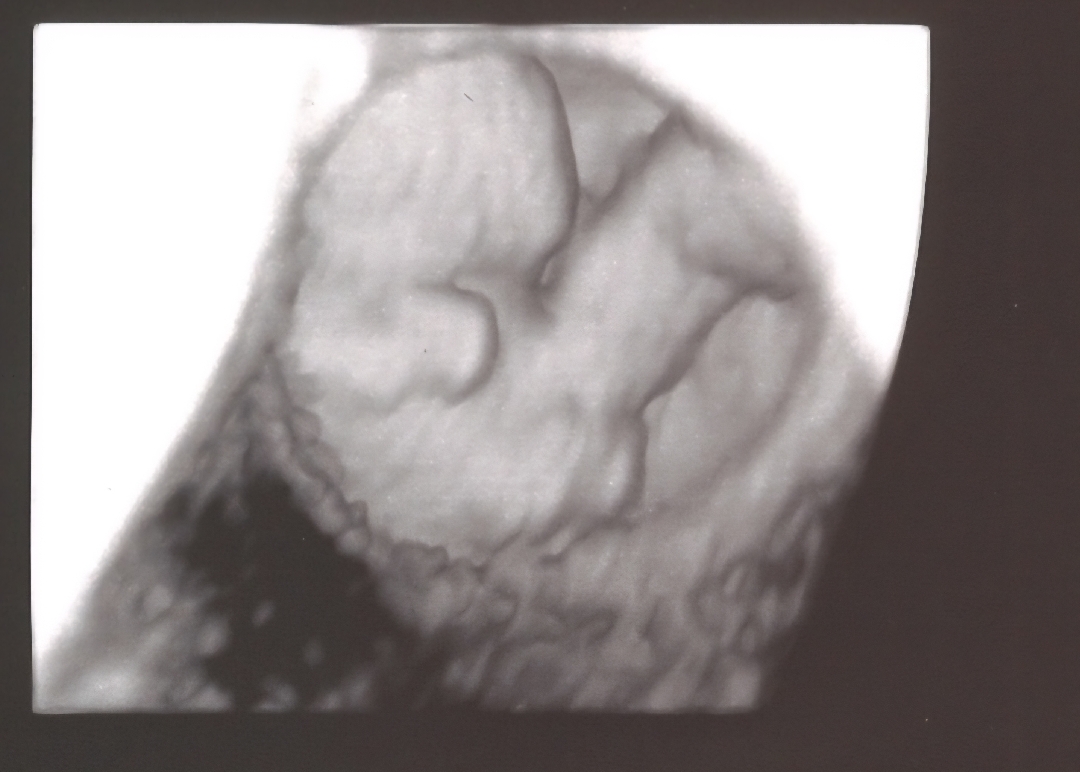

8주차 초음파

8주차 아기 귀여워서 자랑하고 싶어서 공유해요. 첫째랑 잘지내길..

3d처럼 바꾸니깐 저렇게 보이더라고요. 첫째때는 이시기엔 콩만한거만 확인했는데 더 좋은 장비여서 그런 것 같아요.